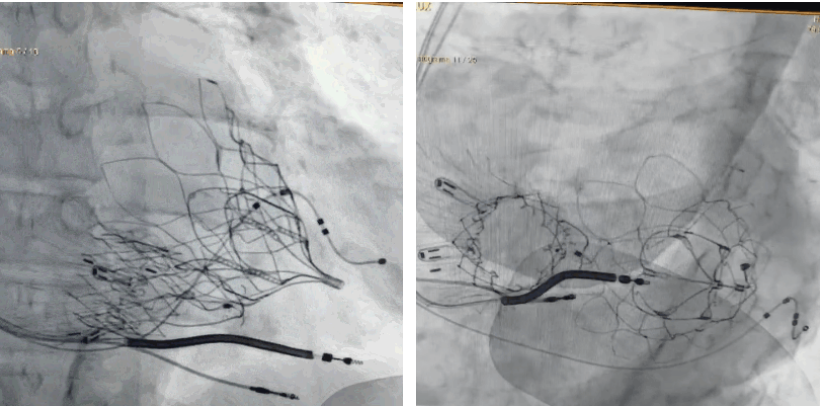

術(shù)后DSA顯示Lux-Valve Plus與Tendyne和ICD無相互影響

手術(shù)在全麻狀態(tài)下進行。術(shù)者采用經(jīng)右側(cè)頸靜脈入路的方式將輸送器送入患者心臟內(nèi),在TEE及DSA引導下調(diào)整輸送器頭端角度,使得輸送器與三尖瓣瓣環(huán)平面垂直。在輸送器進入右心室后釋放室間隔錨定裝置,而后釋放瓣葉夾持件(2個耳片結(jié)構(gòu))成垂直狀態(tài)。在TEE及DSA確定夾持件固定至三尖瓣葉根部且位于右室側(cè)后釋放人工瓣心房側(cè)盤片。隨后調(diào)整瓣膜同軸性以及室間隔錨定件位置(貼合室間隔),前推藏針管并固定,進而釋放室間隔錨定裝置,并再次確認瓣膜位置、穩(wěn)定性及同軸性,合攏輸送鞘后撤出輸送器,完成LuX-Valve Plus人工三尖瓣瓣膜的植入,僅殘余微量瓣周漏。且經(jīng)手術(shù)中心電生理團隊評估,病人的起搏器和ICD功能沒有受到影響。